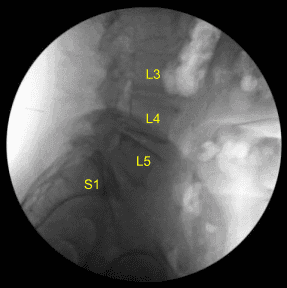

Estaba colocado boca abajo sobre un chasis Jackson Relton-Hall. Todos los puntos de presión estaban cuidadosamente acolchados. Recibieron antibióticos profilácticos intravenosos preoperatorios, ácido tranexámico y dexametasona. La zona lumbar se preparó con una máquina eléctrica de pelo y se limpió con clorhexidina. Se utilizó una aguja espinal calibre 23 y fluoroscopia para localizar el nivel índice.

La unidad C-arm, que estaba cubierta de forma estéril, fue llevada al campo y utilizada para confirmar el nivel. Se fijó un arreglo de neuronavegación en la cresta ilíaca posterior superior derecha con dos clavos de Schanz tras infiltrarse con anestesia local y realizar incisiones #15 en la hoja con puñal.